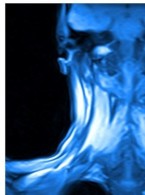

Jak prawidłowo określić długość roboczą kanału z użyciem endometru?

Od kilku lat używam endometru do pomiaru długości roboczej kanału podczas leczenia endodontycznego. Mimo iż staram się opracowywać kanał zgodnie ze wskazaniem endometru, w większości przypadków po wykonaniu zdjęcia rentgenowskiego okazuje się, że przepchnęłam materiał podczas ostatecznego wypełniania kanału. Ponieważ wiem, że w trakcie opracowania wstępnie określona długość robocza może ulec zmianie, tj. może po opracowaniu okazać się krótsza od określonej na początku leczenia, dokonuję zazwyczaj kilkakrotnego pomiaru podczas opracowania kanału, a także bezpośrednio przed wypełnieniem ostatecznym.